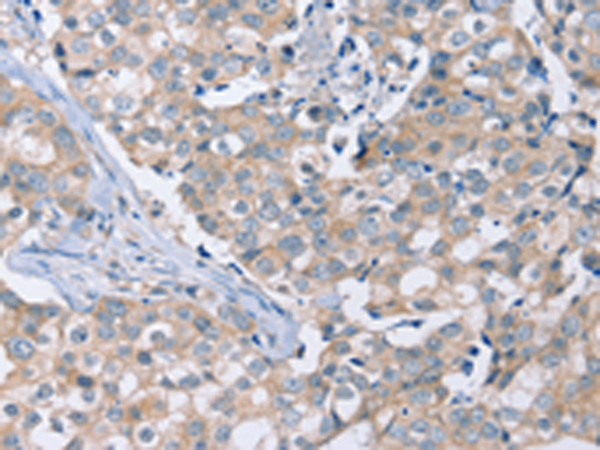

分类: 科研抗体货号: P08593别名: WIG1; WIG-1; PAG608应用: IHC反应种属: Human, Mouse, Rat